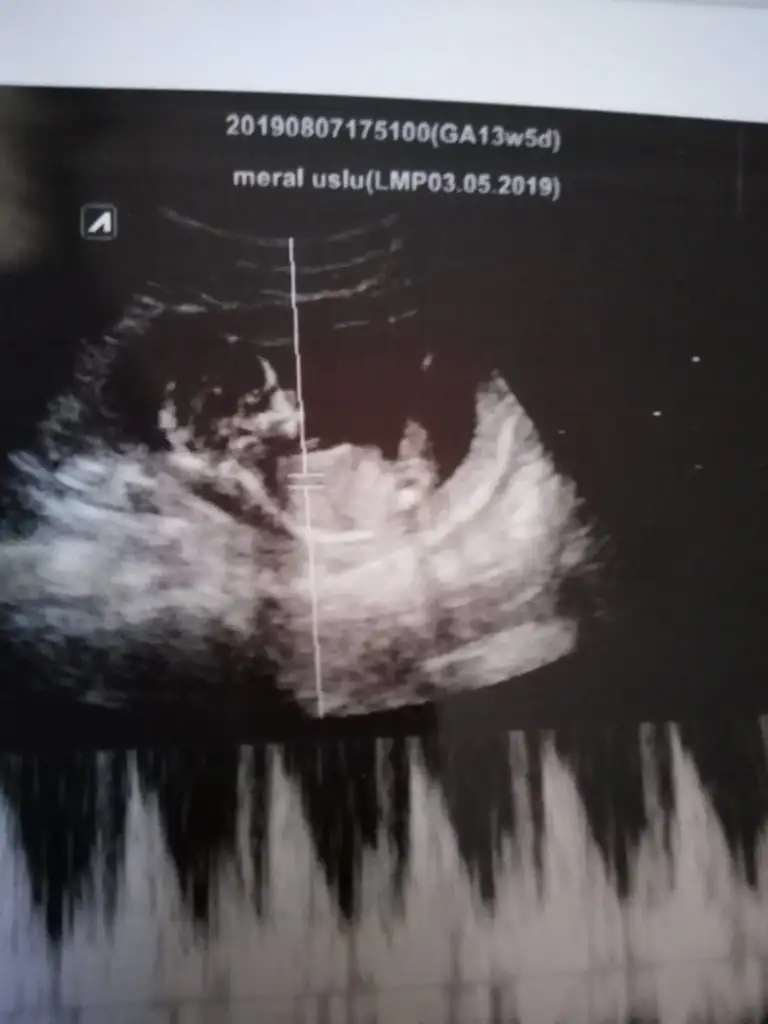

Ramzi Teorisi ve cinsiyet tahmini ( tutma olasılığı %85 miş )

Kızlar 6+1 di burada karından usg yorum yaparmısınız????🙏🏻🙏🏻🙏🏻